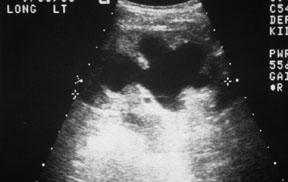

The ultrasound shows left hydronephrosis (grade III on a scale of I - IV). Learn more about ultrasound.